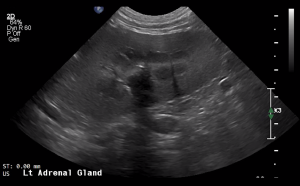

SIMON Ultrasound Database

This ultrasound database is a free resource for students and doctors!

Our collection includes videos of dogs, cats, horses, cows, humans, and many other species!

–Canine and Feline abdominal ultrasound videos were generously provided by the Cummings School of Veterinary Medicine at Tufts University.